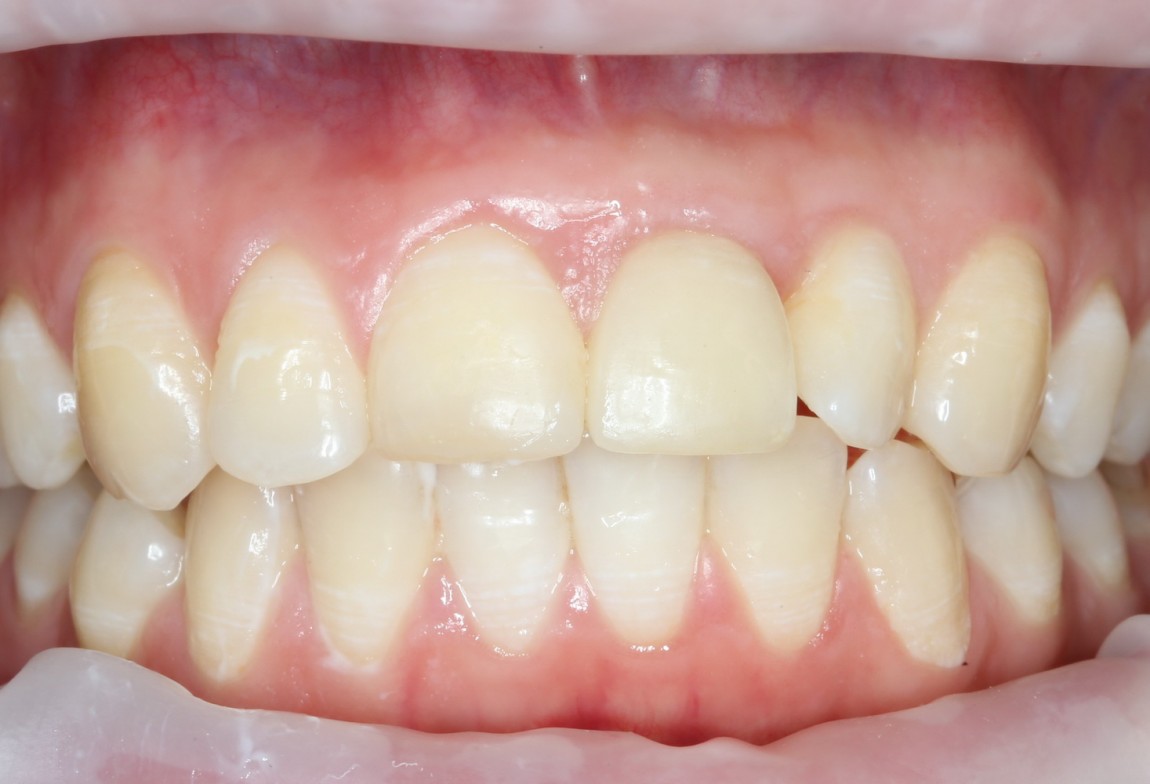

Через несколько месяцев после формирования десны, ортопед изготовил постоянную коронку:

И, на мой взгляд, получилось это очень неплохо. Сравните с тем, что было «до-«:

Наша пациентка это знает, поэтому через год заглянула к нам в клинику. И вот, что мы увидели:

На мой взгляд, это — уже хоть какой-то результат лечения. И, по мнению пациентки, с поставленной задачей мы справились.